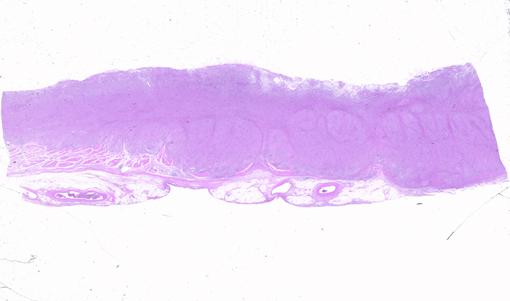

궤양국한형의 위암과 유사한 형태를 나타낸 진행 위 악성 림프종

[Image-ID:2334]

악성 림프계종양/악성 림프종

위(부위)/체부

마이크로

2형(궤양국한형)/

40이상

ss(a1)